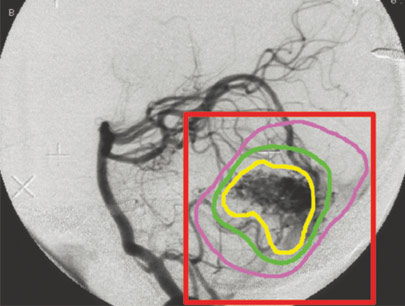

AVM (Arterivenous Malformation)

Kelainan pembuluh darah otak non-stroke

SEBELUM

SESUDAH

(Perempuan, 14 tahun)

Diagnosis: Malformasi Arteri-Vena Oksipital Kanan

Sebelum Gamma Knife

• Nyeri Kepala

3 bulan Setelah Gamma Knife

• Kebutaan menetap

• Penonjolan mata kiri berkurang

Diameter Nidus: 1.5 cm

Nidus tidak ada